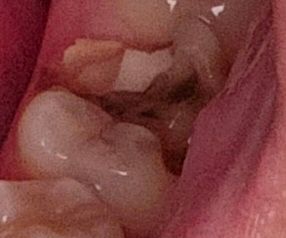

(직접 찍은 치아 사진 포함) 혹시 이정도의 치아 깨짐은 어떤 치료를 받게 되나요?

예전에 치과가서 때운게 최근에 떨어졌다가 오늘은 이가 깨져버렸네요 이거 혹시 치료 받는다면 어떤 치료를 받게되나요 아니면 제가 월요일에 치과를 방문할 예정인데

+ 뜨거운거, 차가운거 마실때 약간씩 시립니다.

해당치아의 반대로만 씹으시고 현재 상태로는

신경치료 후 크라운을 씌우는 치료가 필요합니다